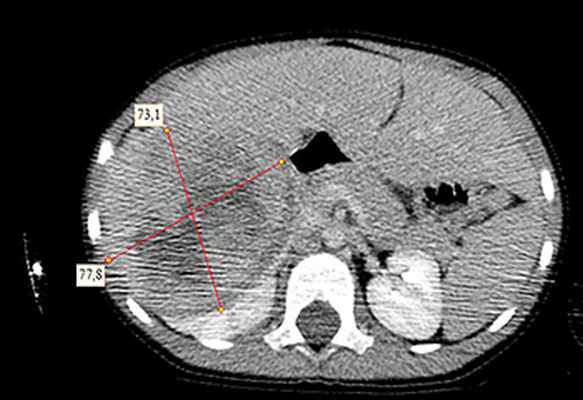

![KT 3]()

Рисунок 3. Контрольная КТ: опухоль после предоперационной химиотерапии. Ребенку проведена предоперационная химиотерапия. На 5-й неделе лечения КТ-контроль показал уменьшение опухоли в размерах до 90ґ80ґ100 мм (см. рис. 3).